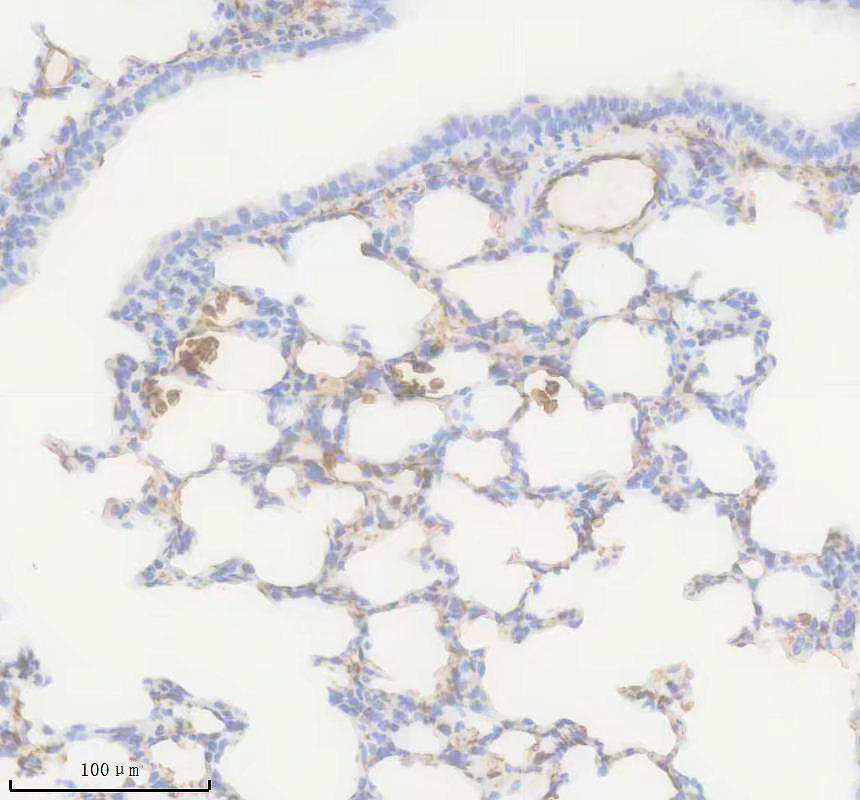

IHC analysis of AQP1 using anti-AQP1 antibody (BM5035).

AQP1 was detected in a paraffin-embedded section of mouse lung tissue. The tissue section was incubated with rabbit anti-AQP1 Antibody (BM5035) at a dilution of 1:200 and developed using HRP Conjugated Rabbit IgG Super Vision Assay Kit (Catalog # SV0002) with DAB (Catalog # AR1027) as the chromogen.